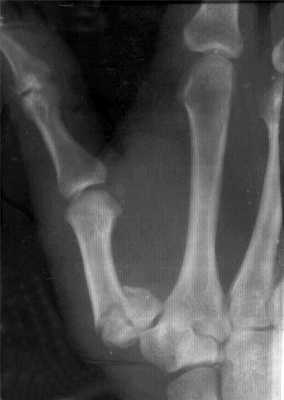

Перелом основания I пястной кости. Характерная травма для боксеров и бойцов MMA. Различают перелом Беннета — отрыв участка основания первой пястной кости, который удерживается связками, с одновременным вывихом ее большей части в запястно-пястном суставе. Перелом Роландо — многооскольчатый переломовывих I пястной кости. Обе травмы проявляются болью, деформацией и отечностью в области “анатомической табакерки” — области под основанием первого пальца — с усилением боли при движении, попытке сжать кулак. Диагностика осуществляется с учетом жалоб, данных анамнеза травмы, осмотра области повреждения и рентгенографии кисти. Лечат переломы Беннета и Роландо хирургическим путем с применением остеосинтеза — восстановления целостности кости путем фиксации отломков металлическими спицами, штифтами или пластинами.

Перелом средней части I пястной кости. Чаще возникает вследствие прямого удара по кости. Проявляется болью, отеком и деформацией в области первой пястной кости. Диагноз устанавливается с учетом жалоб пациента, сведений о механизме повреждения, осмотра области первой пястной кости и рентгенологического исследования костей кисти. Лечение — гипсовая иммобилизация сроком 4-5 недель, при смещении отломков — предварительная закрытая репозиция. При неэффективности консервативной репозиции для сопоставления отломков проводится операция — спицевой остеосинтез.

Пример операции доктора Валеева по восстановлению после перелома первой пястной кости: